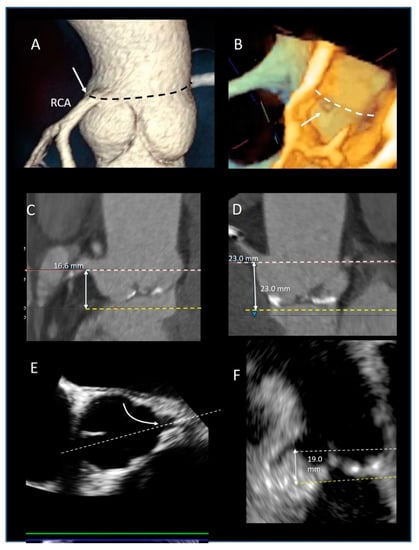

| Ventricular–arterial junction | The term ventricular–arterial junction describes the border between the ventricular myocardium and the fibroelastic structure of the aortic root. Contrary to the right AV junction, where the pulmonary root is entirely supported by the muscular infundibulum, only the left and the right coronary sinuses are partially supported by the myocardium (see text), being the remaining extent of the aortic root supported by fibrous tissue (MS = membranous septum; see text and references [12,13]). | ![]() |